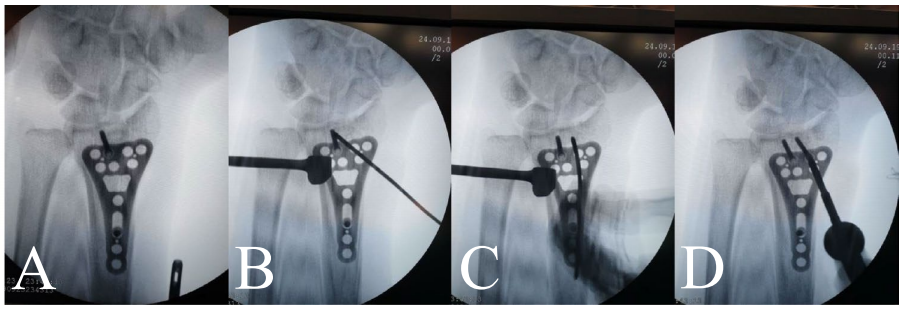

钢板定位在分水岭线近侧,通过尺侧瞄准导向器用1.8mm克氏针临时固定。用C型臂确认位置并进行调整,直至克氏针到达软骨下骨。通过外侧克氏针实现额外固定,随后放置螺钉(先远端螺钉,后骨干螺钉)。通过旋前方肌上的小戳口插入骨干螺钉。如果关节面碎片有塌陷,可通过钢板窗口使用克氏针进行复位(图2)。在关节外骨折中,通过活动腕关节并将骨骼固定到钢板上实现复位。依次插入并拧紧近端和远端螺钉完成最终固定(图1, 3)。使用皮下MONOCRYL 4-0缝线关闭皮肤。在本研究中,对于关节内和粉碎性骨折,使用KLS Martin可变角度锁定加压钢板桡骨远端钢板进行固定;对于简单的关节外骨折,使用SMPL桡骨远端T型板进行固定,两者均为钛合金材质。

图2 复位塌陷的关节面骨块。A 可见塌陷的关节面骨块。B 克氏针穿过骨折部位。C 使用克氏针抬高塌陷的骨块。D 用锁定螺钉固定骨块。